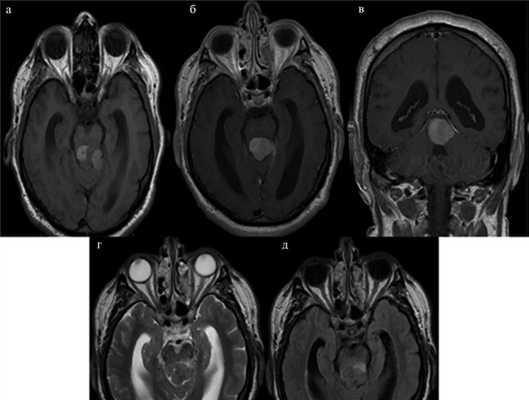

Картина, полученная при МРТ, представлена на рис. 1. Рис. 1. МРТ до операции (аксиальные, сагиттальные и фронтальные томограммы головного мозга, до и после контрастного усиления). а, б, в — томограммы, выполненные в режиме Т1; определяется объемное образование, с четкими ровными контурами, расположенное в пинеальной области, с дорсолатеральным распространением влево; на коронарной плоскости опухоль плотно прилегает к краю намета слева; г — томограммы, выполненные в режиме Т2, опухоль имеет гомоинтенсивный сигнал, четко прослеживается граница между опухолью и стволом головного мозга; д — томограммы, выполненные в режиме T2-FLAIR; визуализируется небольшой перитуморозный и перивентрикулярный отек. Максимальный размер образования составляет 20×26×21 мм.

На серии аксиальных, сагиттальных и фронтальных томограмм головного мозга определялось объемное образование, с четкими ровными контурами, расположенное в пинеальной области, с дорсолатеральным распространением влево. На коронарной плоскости опухоль плотно прилегала к краю намета слева (см. рис. 1, а—в). Опухоль резко деформировала средний мозг, но четко прослеживалась граница между опухолью и стволом головного мозга (см. рис. 1, г). Визуализировался небольшой перитуморозный и перивентрикулярный отек (см. рис. 1, д). Максимальный размер образования составлял до 20×26×21 мм.